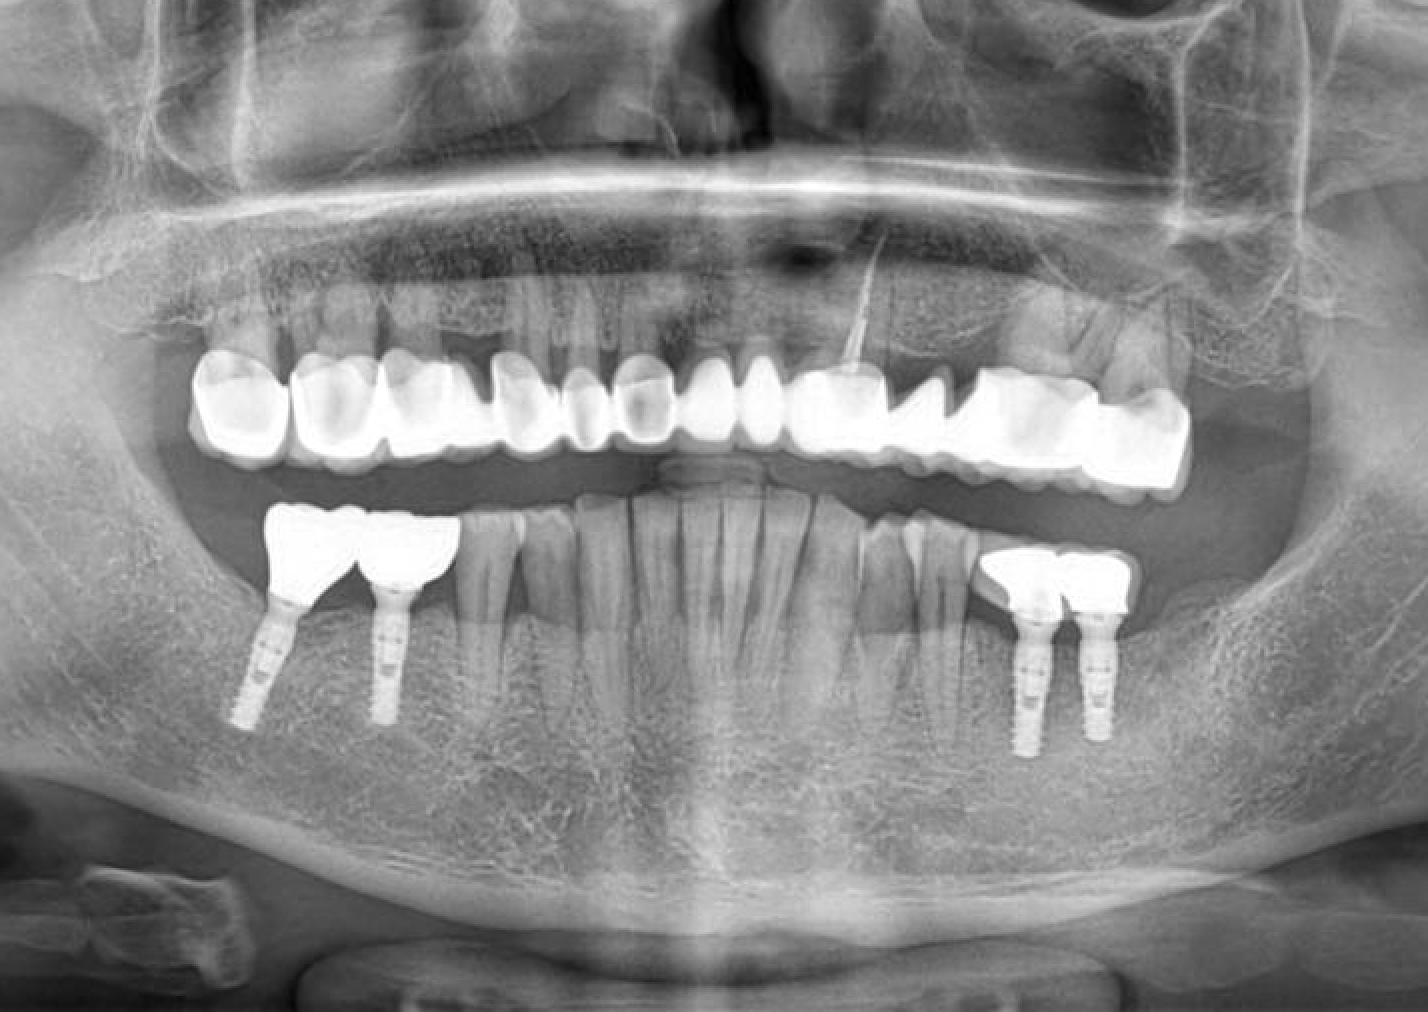

The effects of diabetes, smoking, and alcohol consumption on implant treatment are increasingly being investigated. This case presentation discusses successful implant treatment with Naxis implants in a male patient with high diabetes and heavy smoking-alcohol use. Additionally, X-ray images taken five years after the initial implant surgery are provided to…

Sinus Avoidance Technique: Placement of 4 Upper Jaw and 6 Lower Jaw Implants

In cases where sinus augmentation procedures are not feasible or preferred, alternative techniques must be employed to ensure successful implant placement in the upper jaw. This case presentation discusses the utilization of a sinus avoidance technique for the placement of 4 implants in the upper jaw and 6 implants in…